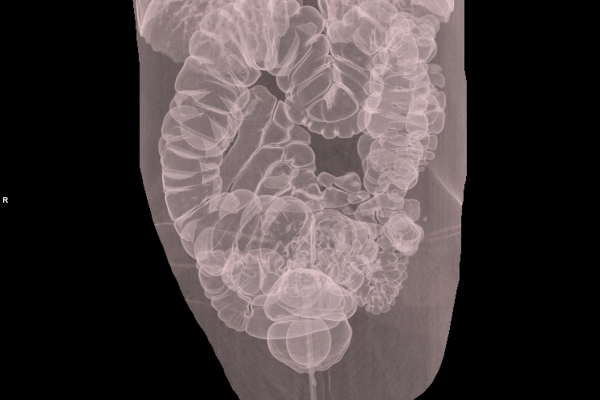

CT Untersuchung Bild

Modernste Bildgebung für jeden Bereich Ihres Körpers

Entdecken Sie, welche CT- und MRT-Untersuchungen in unserer Radiologie für jeden Bereich Ihres Körpers möglich sind.

Wir bieten ein breites Spektrum an Untersuchungen an, von Standarduntersuchungen der Gelenke, Organe oder großflächigen Körperregionen bis zu Spezialuntersuchungen zum Beispiel des Herzen oder der Gefäße. Zusätzlich werden Angiographien (Darstellung von Blutgefäßen), Endometriose-Abklärungen und Mamma-Untersuchungen durchgeführt. Genauere Details können Sie der MRT/CT-Übersicht und der Preisliste entnehmen, oder Sie wenden sich direkt an unser Team, das Sie gerne zur passenden Untersuchung berät.

Was ist der Unterschied zwischen einer MRT- und einer CT-Untersuchung?